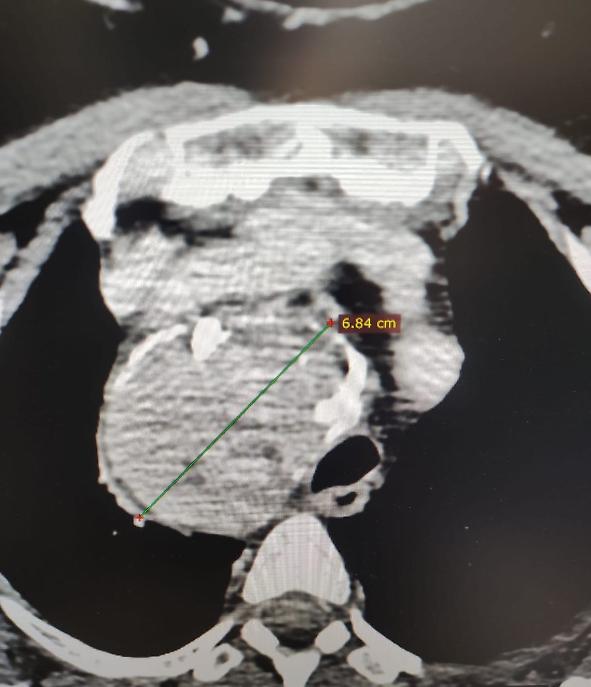

“Gli accertamenti radiologici hanno evidenziato una tiroide ingrandita di circa 7 centimetri, che si estendeva nel mediastino spingendo la trachea verso sinistra – spiega il dottor Luigi Madami, otorinolaringoiatra che ha eseguito l’intervento sotto la direzione del professor Nicola Quaranta –. Erano presenti anche piccoli noduli e calcificazioni, e l’unica soluzione possibile era la rimozione chirurgica completa della ghiandola”.